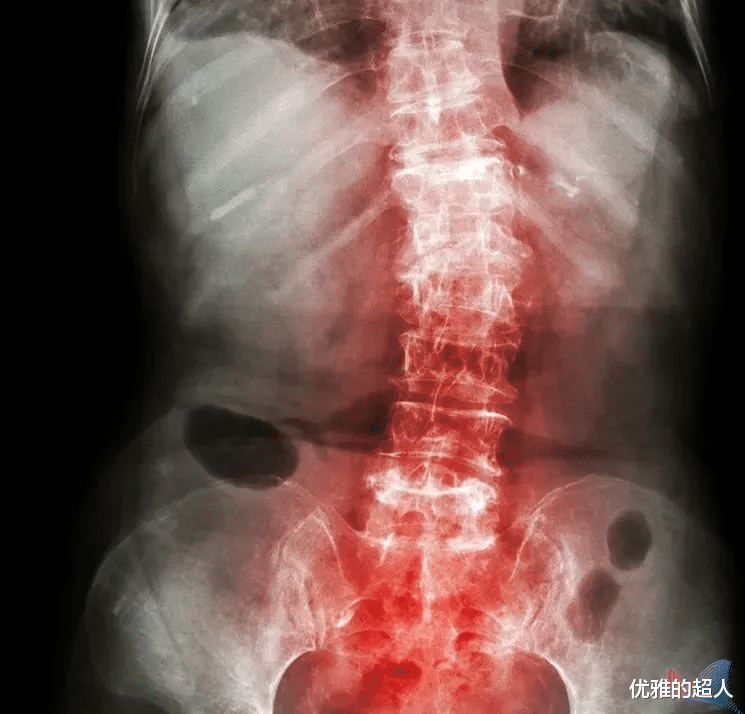

强直性脊柱炎最常见的症状为腰背部或者骶髂部疼痛,有些还伴有晨僵,半夜痛醒,翻身困难,活动后症状减轻。

因此,当出现腰、背、颈、臀、髋部疼痛以及关节肿痛,很有可能是强直性脊柱炎,但是这些症状不足以诊断疾病,需要辅助检查进一步确诊,常用以下几种方法:X线检查、CT检查、骶髂关节MRI、化验检查。

晚期症状包括: 1、脊柱严重强直,严重的脊柱畸形; 2、关节严重畸形,这些晚期症状将使患者的脊柱或(和)髋关节功能丧失而致残,最终严重影响患者的生活质量。 遗憾的是,强直性脊柱炎没有有效的预防方法,如果出现上文提到的症状,请尽快到免疫风湿科做详细检查。 如何治疗及预防?